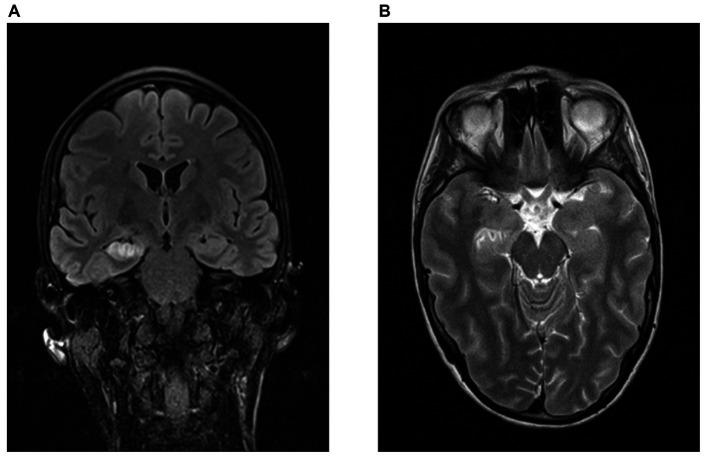

The overall olfactory function of the AE-group and the PC-group was comparable (mean TDI 32.0 [CI 27.3-36.7], 32.3 [CI 28.5-36.0)]. The proportions of hyposmic patients were similar compared to the general population. However, AE patients of the non-NMDAR group had significantly lower TDI-scores (28.9 ± 6,8) than NMDAR patients (37.4 ± 3.5) ( = 0.046) and a significantly lower discrimination capability than the NMDAR patients (9.9 ± 2.0 vs. 14.5 ± 0.6) ( = 0.002). The non-NMDAR patients had significantly more limbic MRI pathologies (6/7) compared to the NMDAR patients (0/4) ( = 0.015). Furthermore, a correlation between limbic MRI pathologies and worse capability of smelling discrimination was found ( = 0.016,  = -0.704,  = 11).

AE组和PC组的总体嗅觉功能相当(平均TDI分别为32.0 [CI 27.3 - 36.7],32.3 [CI 28.5 - 36.0])。嗅觉减退患者的比例与一般人群相似。然而,非NMDAR组的AE患者的TDI评分(28.9±6.8)显著低于NMDAR患者(37.4±3.5)(p = 0.046),且辨别能力显著低于NMDAR患者(9.9±2.0对14.5±0.6)(p = 0.002)。与NMDAR患者(0/4)相比,非NMDAR患者有更多的边缘系统MRI病变(6/7)(p = 0.015)。此外,发现边缘系统MRI病变与嗅觉辨别能力较差之间存在相关性(p = 0.016,r = -0.704,n = 11)。

结论

我们的结果表明,NMDAR自身免疫性脑炎患者的长期嗅觉功能正常。然而,非NMDAR自身免疫性脑炎患者似乎存在持续受损的嗅觉功能,可能是由边缘系统结构的脑炎损伤介导的。